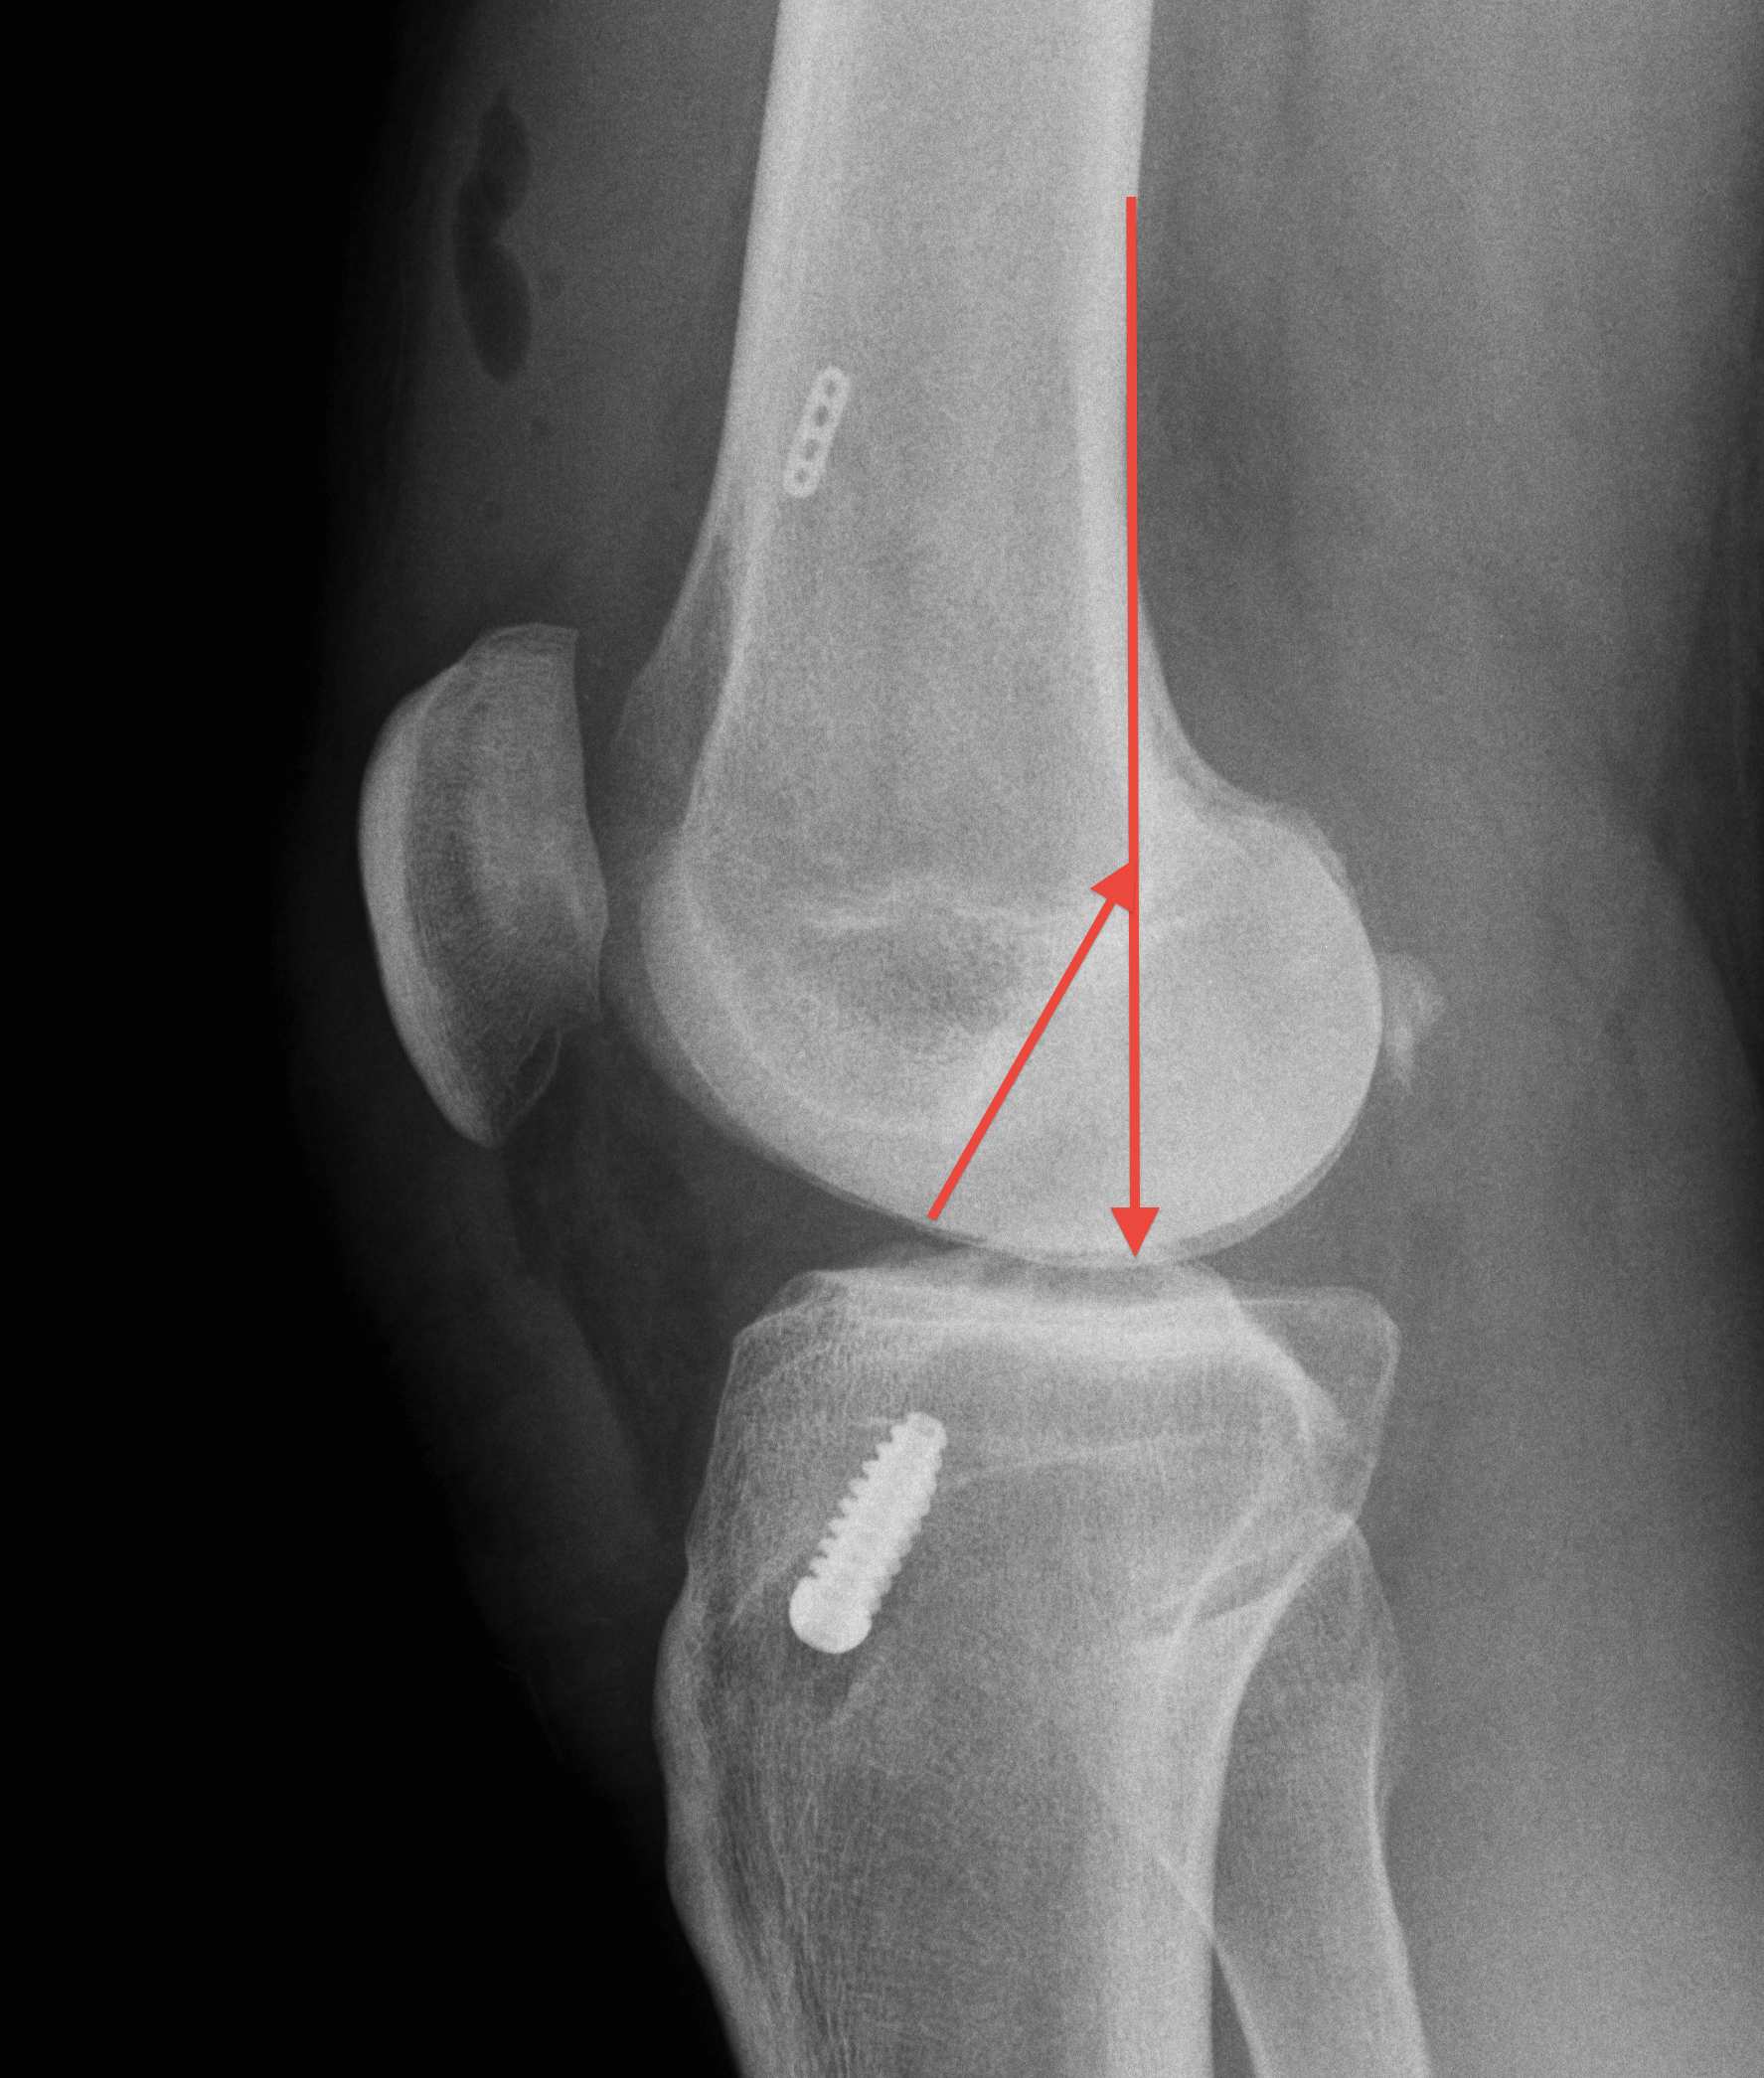

2. X-ray assessment

Lateral x-ray

Femoral tunnel

- intersection of line posterior femoral cortex and Blumensaat's line

Tibial tunnel

- posterior to Blumensaat's line in full extension

- parallel to Blumensaat's line

C. Vertical Graft

Fu etal Arthroscopy 2003

- cadaver study of graft in 10 v 11 o'clock position

- demonstrated increased rotational instability in 11 o'clock